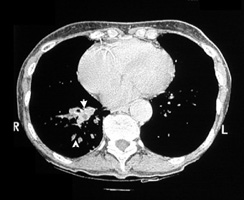

Bronchiectasis

Dilated bronchi with peribronchial fibrosis, visualized in various cuts of CT as cystic spaces, tubular shadows and branching densities.